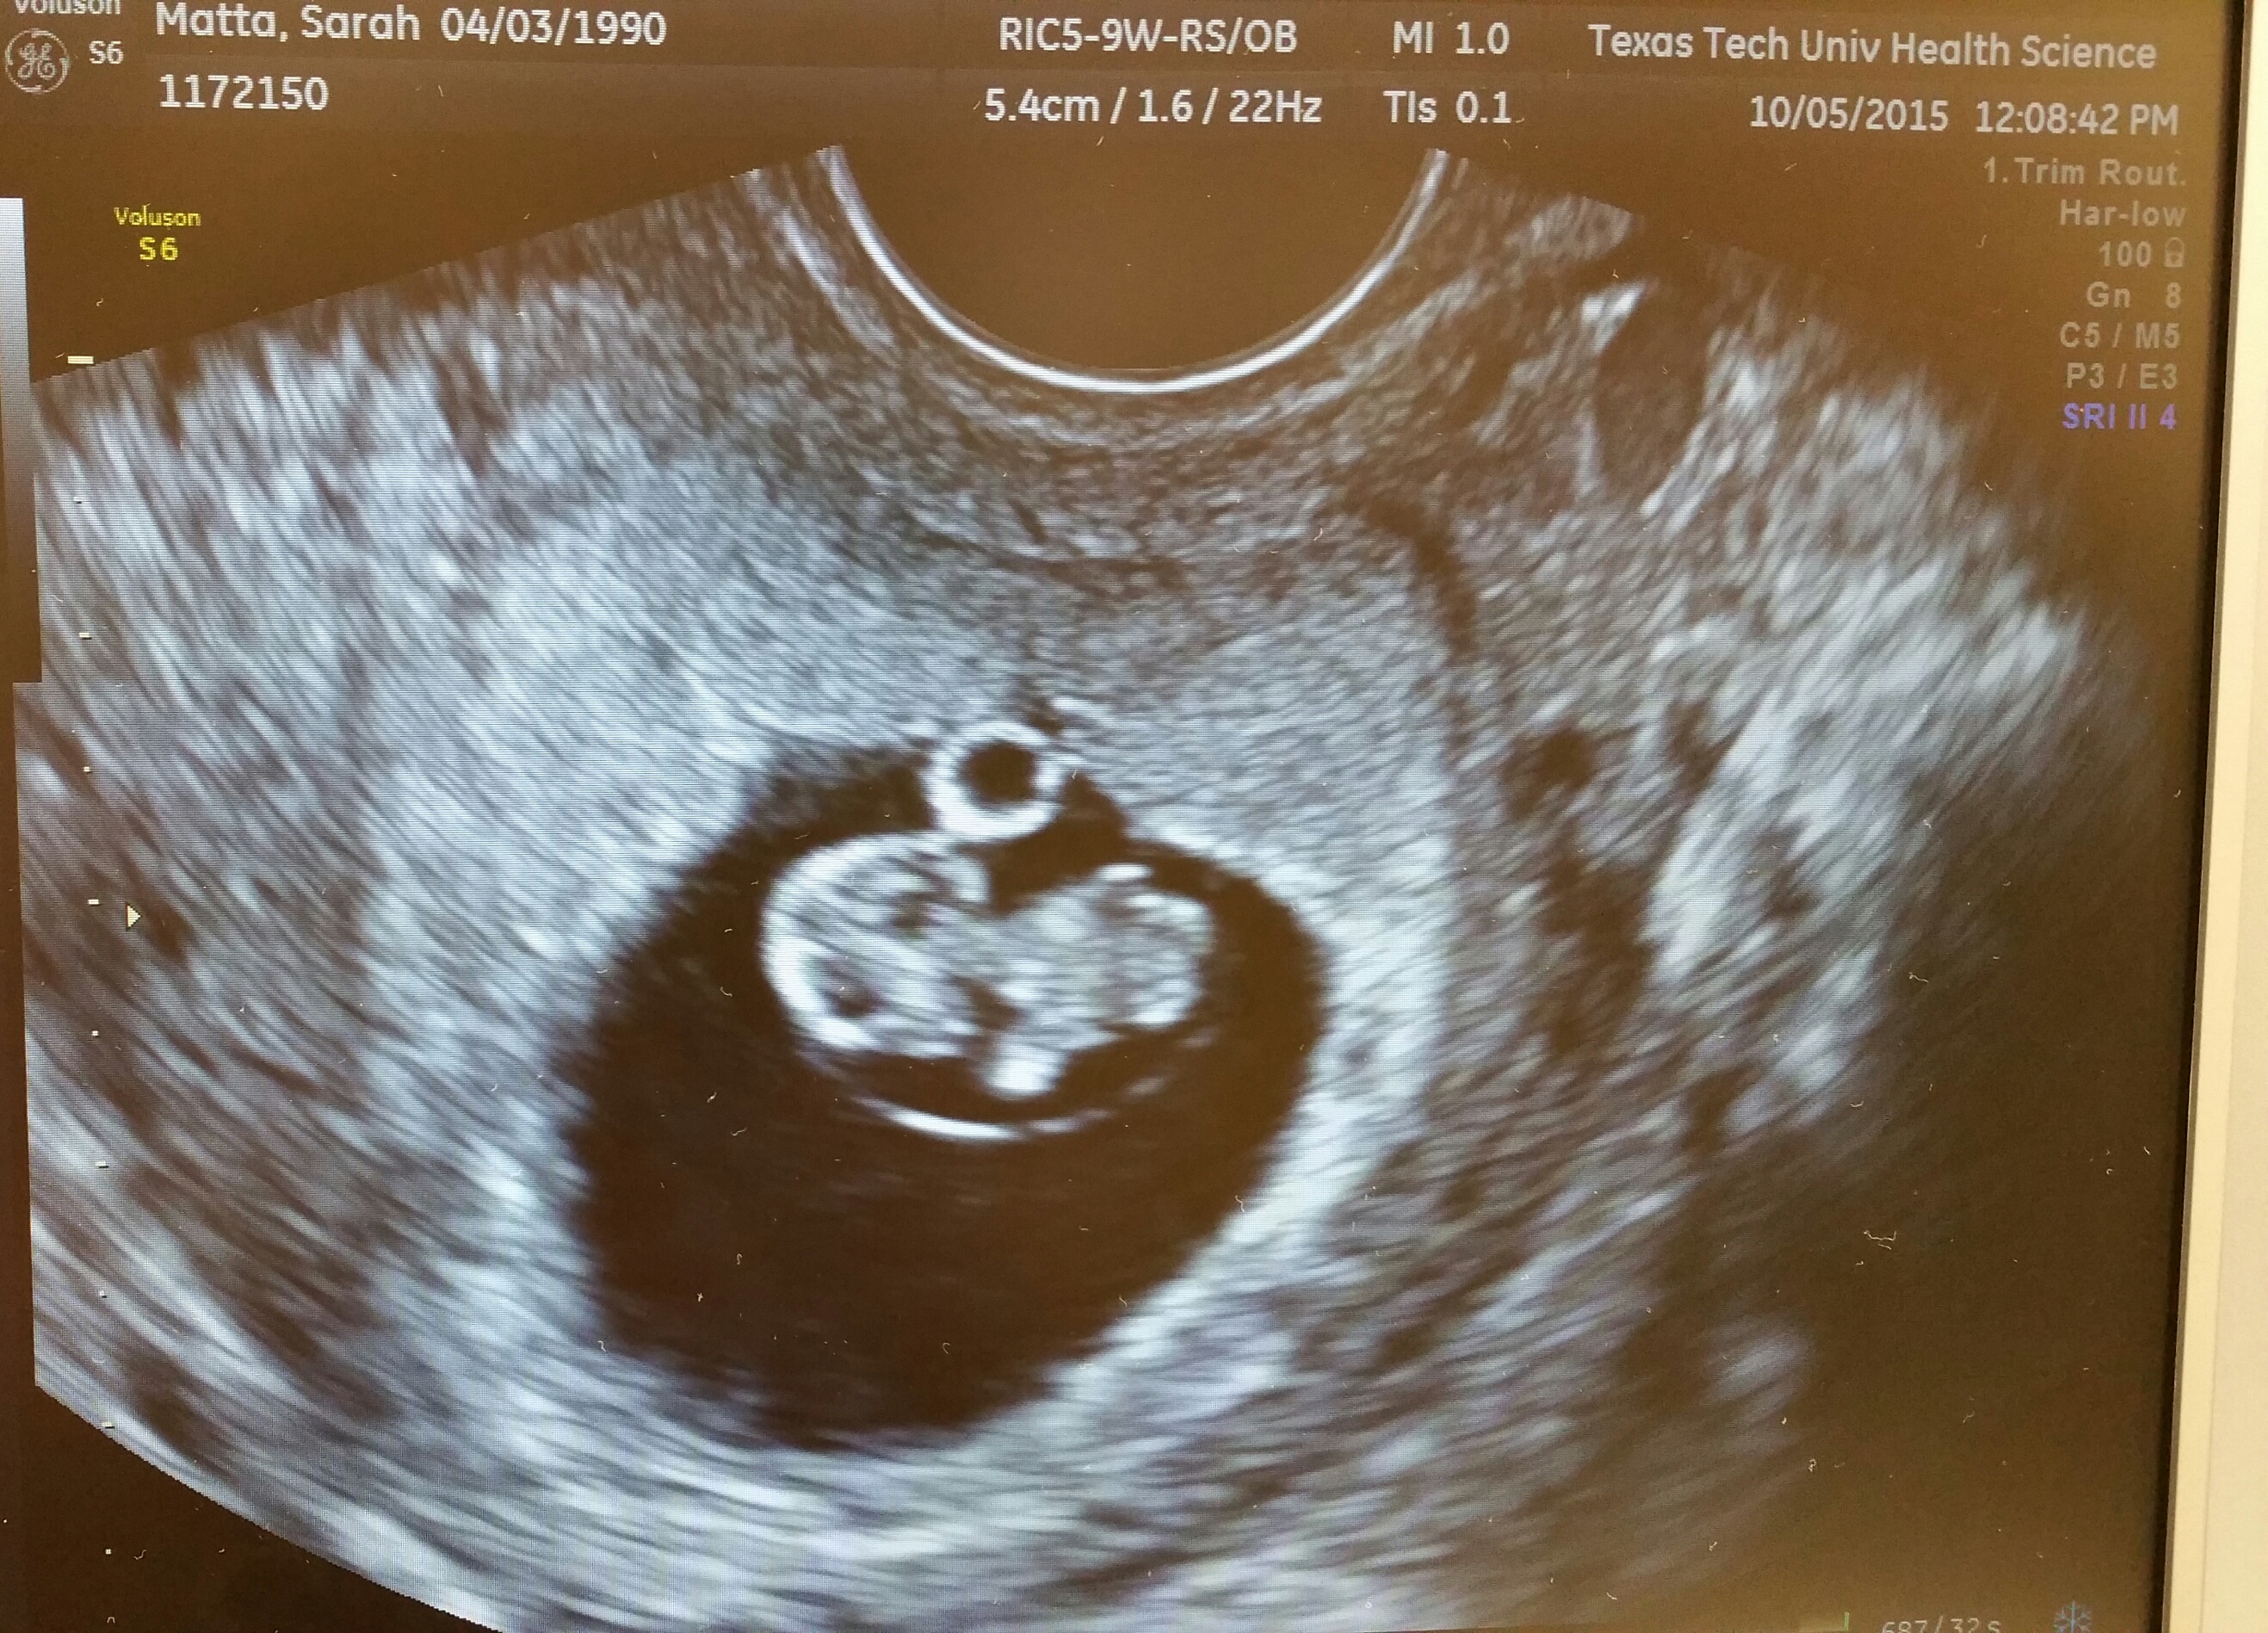

Had our first appointment yesterday. Baby measured right on track at 9w1d with a due date of May 10th! Very grateful that everything is going well so far.

8 week ultrasound and there's twins! We were only able to see one heart beat and they thought I'm a week behind where I thought I was so please send good growing thoughts my way. Headed back in a week to hear Baby B. also if anyone has had experience in this area, please advise.

8 week ultrasound and there's twins! We were only able to see one heart beat and they thought I'm a week behind where I thought I was so please send good growing thoughts my way. Headed back in a week to hear Baby B. also if anyone has had experience in this area, please advise.</p>